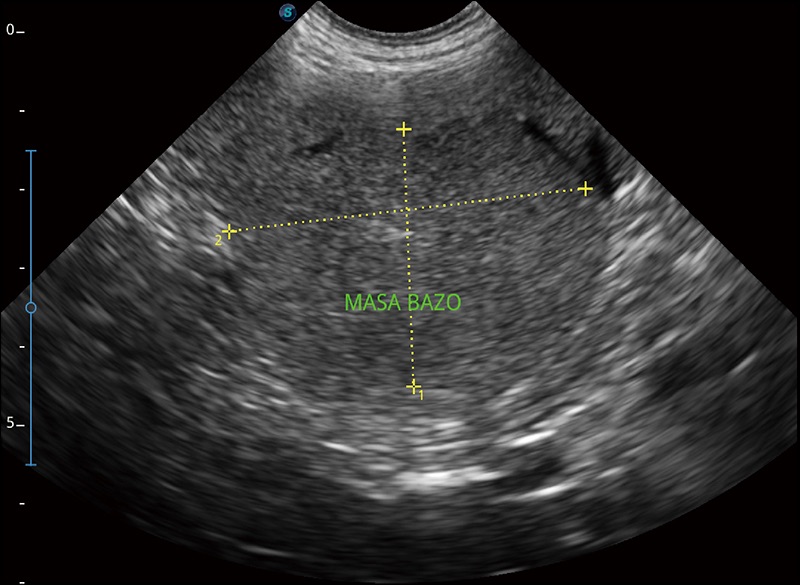

实时宽景成像

可实时观察感兴趣区域和病变位置